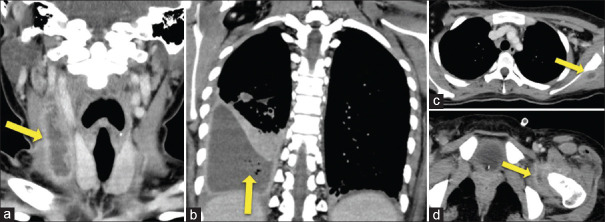

We present a 19-year-old woman, a case of Lemierre syndrome, who presented with fever, sore throat, and left shoulder pain. Imaging revealed a thrombus in the right internal jugular vein, multiple nodular shadows below both pleura with some cavitations, right lung necrotizing pneumonia, pyothorax, abscess in the infraspinatus muscle, and multiloculated fluid collections in the left hip joint. After inserting a chest tube and administering urokinase for the pyothorax, a bronchopleural fistula was suspected. The fistula was identified based on clinical symptoms and computed tomography scan findings. If a bronchopleural fistula is present, thoracic lavage should not be performed as it may cause complications such as contralateral pneumonia due to reflux.

我们为您介绍一名 19 岁女性莱米埃尔综合征患者,她因发热、咽喉痛和左肩疼痛而就诊。影像学检查显示右颈内静脉有血栓,双侧胸膜下方有多个结节状阴影,并伴有一些空洞,右肺坏死性肺炎,脓胸,冈下肌脓肿,左髋关节有多发性积液。在插入胸管并使用尿激酶治疗脓胸后,怀疑出现了支气管胸膜瘘。瘘管是根据临床症状和计算机断层扫描结果确定的。如果存在支气管胸膜瘘,则不应进行胸腔灌洗,因为这可能会导致并发症,如因反流而引起的对侧肺炎。